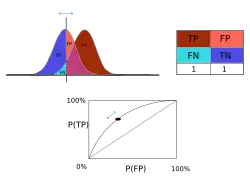

- Image quality can also be assessed using descriptive statistics, e.g. accuracy, sensitivity and specificity, with large patient cohorts and validated diagnoses. Here, a truth table is constructed which details the number of true and false, positive and negative radiology interpretations - see Figure 6.21. Note that this perspective is similar to that adopted in the famous Known Knowns remark used in US politics!

- Receiver Operating Characteristic (ROC) curves can be derived from such cohort data. This method is based on signal detection theory, where human observers score their level of confidence for their interpretations of the image data. ROC curves are obtained by plotting the probability of true positive results against that of false positives. A diagonal line is obtained in the case of random decisions and actual curves lie above this line. Decision levels towards the extreme top right of the curve is referred to as Over-Reading while those close to the origin are referred to as Under-Reading. A major advantage of such data analysis is that it yields a single number - the area under the ROC curve - which describes the overall performance of a diagnostic system. It should be appreciated, however, that ROC analysis requires the availability of a superior standard of truth, e.g. biopsy results, an adequate number of diseased and control subjects as well as a number of qualified observers.